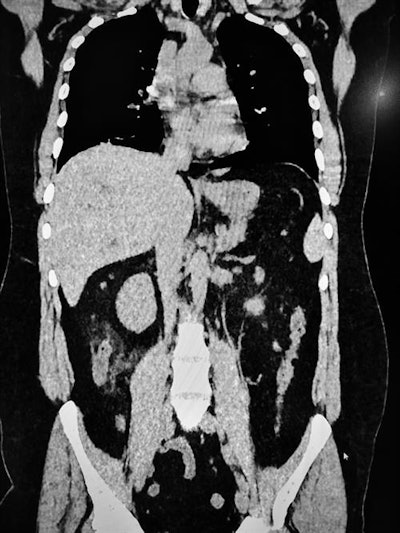

Thanks to the national and international publications and information campaigns, we have become quite aware of the COVID-19 CT features, but soon we had quite a lot of nontypical cases, including patients with extrathoracic findings or severe cases in young people. We have also had some patients from our hemodialysis center presenting with less severe cases and many patients with ear, nose, and throat symptoms or associated diseases, including pulmonary emboli. This is quite a problem in COVID-19 cases that require cooperation with clinicians, especially emergency specialists.